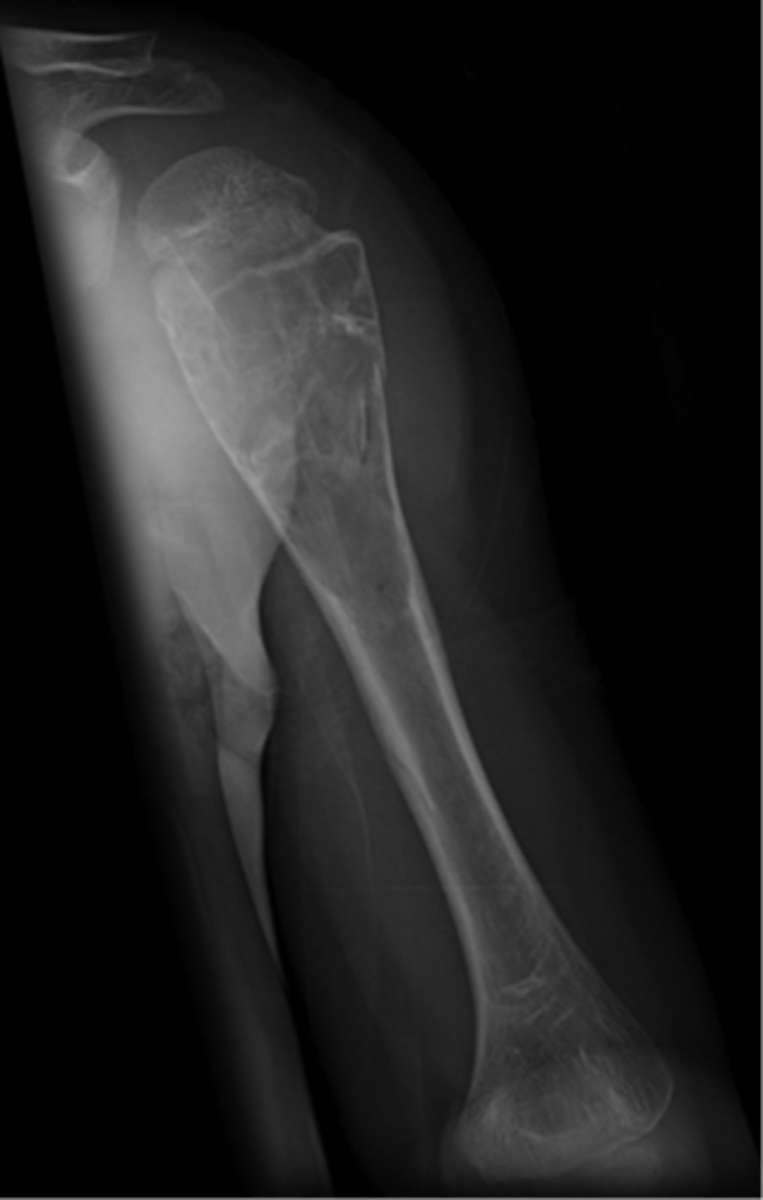

Aneurysmal bone cyst

- 1% of biopsied primary bone tumors

- M:F, 2:3

- 5-20 y.o.

- Acute pain

- Previous trauma

- 80% tubular bones and spine

<p>- 1% of biopsied primary bone tumors</p><p>- M:F, 2:3</p><p>- 5-20 y.o.</p><p>- Acute pain</p><p>- Previous trauma</p><p>- 80% tubular bones and spine</p>

- Eccentric

- Metaphyseal

- Osteolytic with fine trabeculae

- Saccular ballooning of cortex

- May cross epiphysis

- Periosteal buttressing

State the radiographic features of aneurysmal bone cyst in tubular bones

<p>State the radiographic features of aneurysmal bone cyst in tubular bones</p>